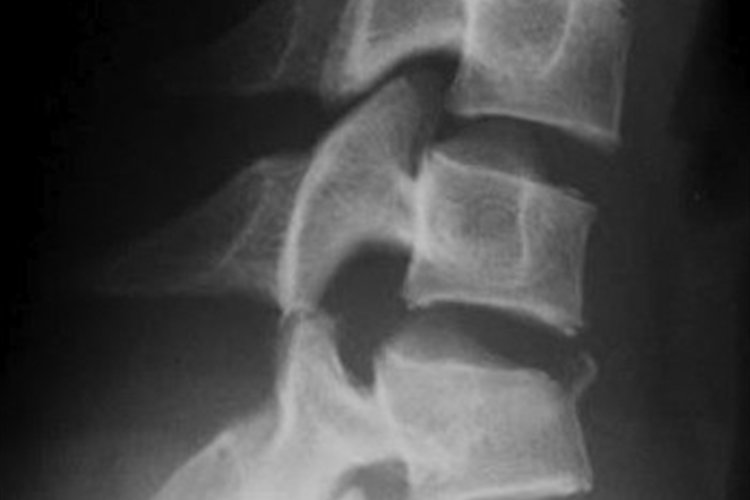

Patient avec douleurs cervicales après un accident de voiture de faible cinétique. Diagnostic?

Entorse cervicale car antélisthésis, pincement antérieur, perte du parallélisme des vertèbres et augmentation de l’écart inter-épineux

/!\ risque luxation